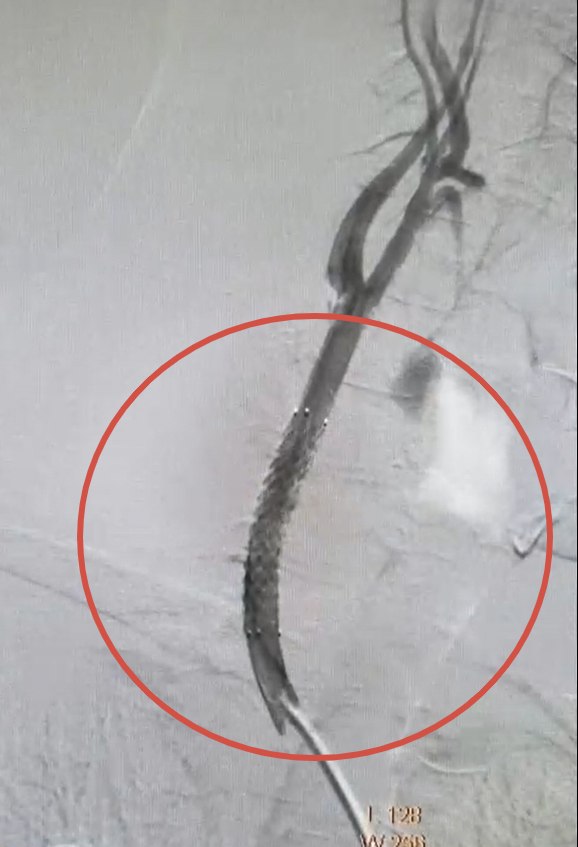

Под местным обезболиванием специалисты Валерий Казанов и Алексей Подтуркин проделали маленький надрез в бедренной артерии ноги. Используя точное рентгенологическое оборудование нового ангиографического комплекса, врачи ввели миниатюрные инструменты по сосудам до поражённого участка шеи. Затем в артерию установили стент-графт — надёжную трубку из полиэстера с металлической опорой. Она усилила слабую стенку сосуда, защищая его от возможного разрыва. Операция длилась примерно час.

«Мы устранили аневризму изнутри кровяного русла, продвигаясь непосредственно по самим сосудам. Это минимизирует нагрузку на организм больного и существенно ускоряет восстановление», — рассказал Леонид Беликов, главный сосудистый хирург министерства здравоохранения Курской области.